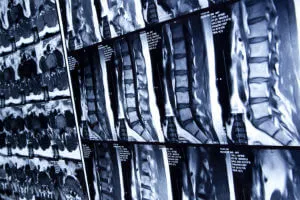

What Is a Spinal Cord Injury?

A spinal cord injury is damage to any part of the spinal cord or the nerve endings. These injuries often result in paralysis and permanent changes and loss of sensation to areas below the injury site.